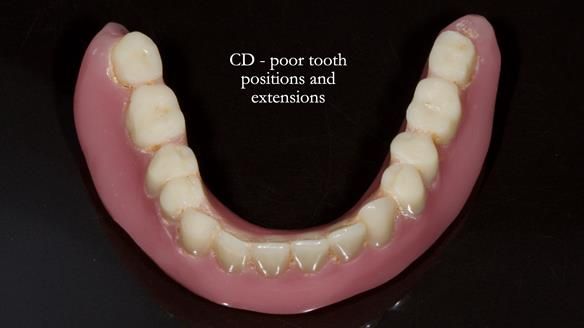

Welcome to Newsletter 83. This month I am sharing Sheila’s case — a very challenging but rewarding complete denture case. Sheila had flat ridges, a small mouth opening, a large tongue and had never been able to wear complete dentures of any kind. Everything was loose and sore. She felt embarrassed and looked older without dentures. She wanted a stable, comfortable result, and she wanted to avoid implants because she has taken bisphosphonates for more than five years.

Because her denture space anatomy was limited, I took two working impressions at the same visit. She had very little space in the lower jaw because of the spread of the tongue and the fact she had never worn a lower denture. This made it difficult to judge exactly where the borders needed to be and how much functional space we truly had.

In Sheila’s case, the Dr Abe shaped impression gave a more stable and comfortable result. Sheila preferred the shape produced by the Abe method, so that is the one we used for the registration rims, the trial denture and the final dentures. But making both impressions was worthwhile. It meant we had every option covered and could choose what worked best for her mouth.